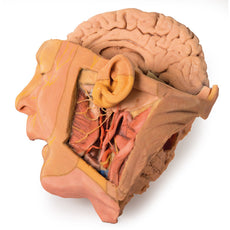

The deep level of dissection has exposed parts of the infratemporal fossa

(through partial removal of the mandibular ramus and corpus) and dissection

of retromandibular tissues. At the inferior margin of the dissection window,

the cut edge of the retromandibular vein lies adjacent to the submandibular

gland and the ascending path of the facial artery as it cross towards to angle

of the mouth. Just superior to the cut retromandibular vein is the posterior

belly of the digastric muscle, overlying a small exposure of the deeper

internal jugular vein.

Just posterior to the retained ascending ramus of the mandible are the

external carotid artery and the occipital artery (running in parallel prior

to passing posteriorly). Tracing the external carotid artery superiorly, the

posterior auricular artery, superficial temporal artery, and maxillary artery are

all visible. The maxillary artery passes deep to the lateral pterygoid muscle

and into the infratemporal fossa, reappearing superior to the lateral pterygoid

as it passes into the pterygomaxillary fissure. Along its course, it gives rise

to the posterior deep temporal artery, the inferior alveolar artery (which is

exposed in the dissected mandibular corpus), the anterior deep temporal

artery, and the posterior superior alveolar artery. Finally, the inferior alveolar

nerve can be seen coursing within the opened mandibular corpus, and the

lingual nerve resting on the medial pterygoid. The buccinator muscle is also

retained, with the distal part of the parotid duct preserved as it enters the

muscle towards the oral mucosa